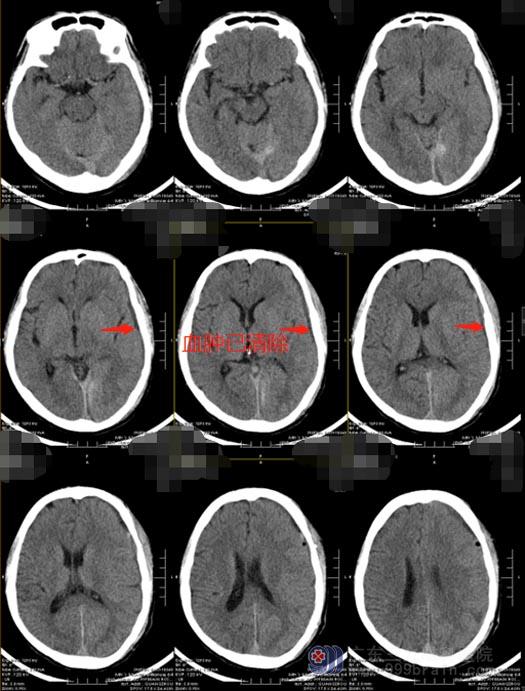

恰巧,陈先生在广州工作的亲戚回家省亲,听闻陈先生的事情后,建议他转至上级医院。他们连夜自驾车十几个小时将陈先生送到广东三九脑科医院。急诊入住神经外五科后,立即复查了头颅CT,显示:1.左侧额颞顶枕硬膜下亚急性血肿;2.左侧枕部大脑镰血下积血;3.创伤性蛛网膜下腔出血;4.右侧颈内动脉虹吸段钙化灶。

慢性硬膜下血肿的形态非常有特征性,其形态如新月,见到脑内出现“新月”,基本上确定为本病无疑了。慢性硬膜下血肿是发生在硬脑膜和蛛网膜之间的血肿,是非常普遍的神经外科疾病,早期症状不明显,CT常出现少量蛛网膜下腔出血,患者主要表现为慢性颅内压增高症状、神经功能障碍以及智能和精神症状,可伴有头痛偏瘫,也有一些患者无自觉症状,当血肿累积到特定量可能会危及患者生命。